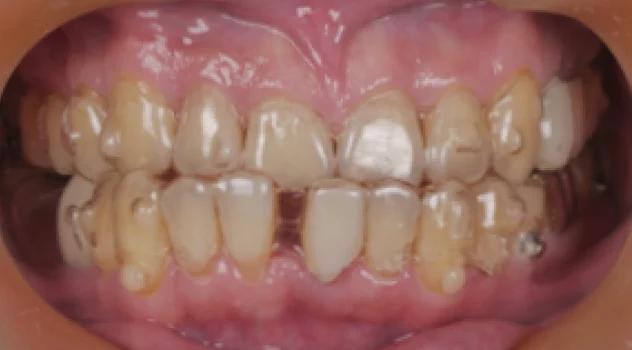

矯正案例-開咬

開咬案例

開咬指的是上下前牙無法接觸,最常聽到的抱怨就是麵咬不斷,⼤部分案例

需要透過拔牙才有辦法改善開咬,此案例透過隱適美與骨釘將上下前牙向內

退縮,除了排⿑牙⿒亦能改善開咬!